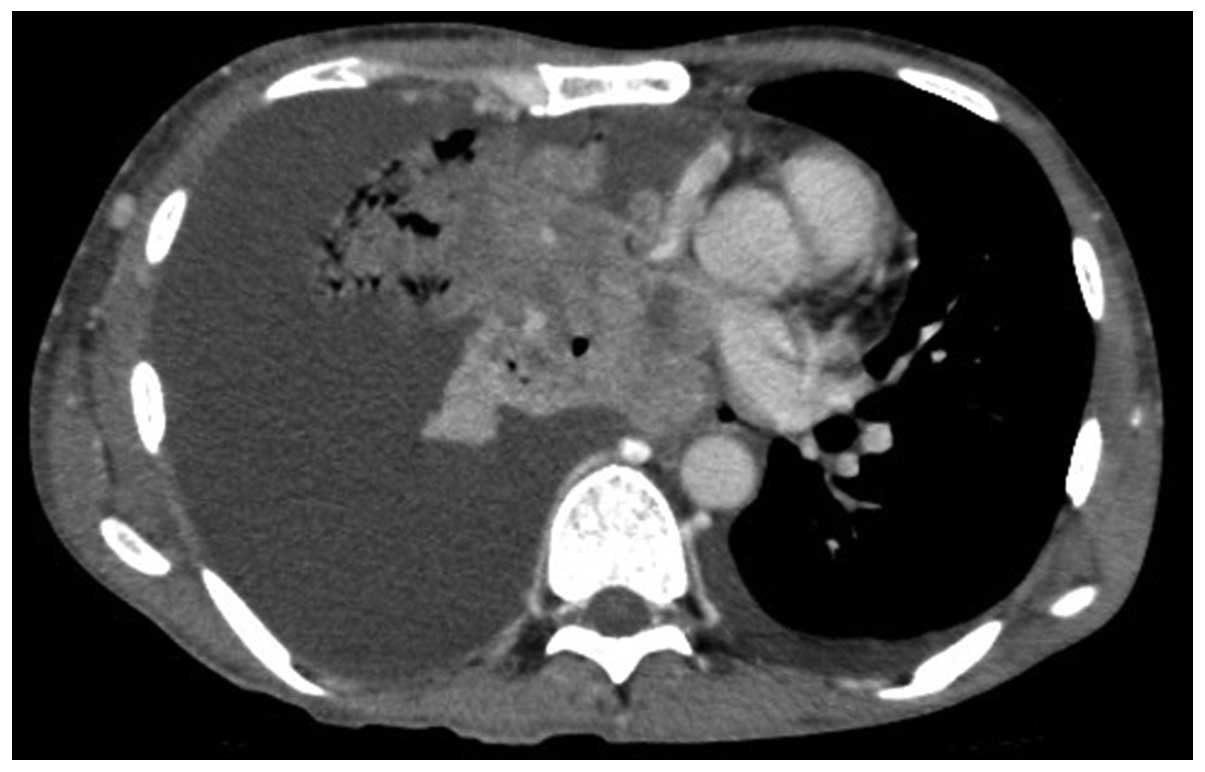

As fluorescence in situ hybridization revealed a translocation of ALK, the patient received crizotinib therapy. After one month, the physical examination and chest CT revealed a significant decrease in the maximum aggregate tumor measurement. The tumor response was classified as PR, but the treatment was discontinued due to crizotinib-related grade 3 general fatigue, according to the National Cancer Institute-Common Toxicity Criteria, version 2.0. The patient declined additional treatment and all the lesions, including the primary site and cervical, axillar, mediastinal and abdominal lymph node metastases, increased in size. A chest CT scan revealed a large mass with a massive pleural effusion (Fig. 1). One year after the discontinuation of crizotinib, the patient consented to receiving alectinib. After 2 weeks of alectinib treatment, a chest CT revealed a significant decrease in the maximum aggregate tumor measurement (Fig. 2). The tumor response according to the RECIST guidelines was classified as PR. Adverse events, including general fatigue, were not observed. At 4 weeks after the initiation of alectinib, the patient remained alive and adverse event-free.

Figure 2.

Chest computed tomography (CT) scan 2 weeks after alectinib initiation revealing a significant decrease in the maximum aggregate tumor measurement.